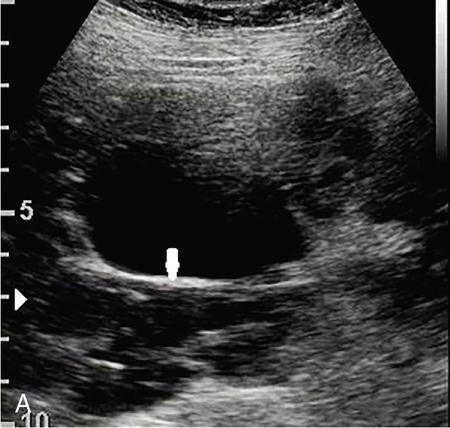

Drushi Patel CONTRAST-ENHANCED ULTRASOUND IN ADULT GENITOURINARY IMAGING Mridula Muthe Ultrasound is the initial screening examination for the evaluation of the renal morphology and suspected renal lesions due to its multiple advantages such as easy accessibility, bedside assessment, affordability and lack of radiation. Vascularity of the kidney and renal lesions can be studied with the use of colour Doppler ultrasound however, it provides information only about the macrovasculature. With the use of microbubble ultrasound contrast agents (UCAs) macro as well as the microvasculature can be studied. Contrast-enhanced ultrasonography (CEUS) is also more sensitive than Doppler ultrasound as it is not affected by blood velocity and angle of insonation of the ultrasound beam. In urology, the established applications of CEUS in adults include characterization of cystic lesions and differentiation between pseudotumours and solid lesions. Box 10.23.1.1 provides a list of European Federation of Societies for Ultrasound in Medicine and Biology (EFSUMB) recommended indications of CEUS in renal evaluation. EUROPEAN FEDERATION OF SOCIETIES FOR ULTRASOUND IN MEDICINE AND BIOLOGY (EFSUMB) RECOMMENDED INDICATIONS FOR USE OF UCA IN RENAL EVALUATION Renal ischaemia. Evaluation of solid renal lesions. Differentiation between solid renal lesions and pseudotumours. Characterization of complex cystic masses. Characterisation of indeterminate renal masses. Renal infections. Follow-up of nonsurgical complex masses. To improve lesion visualization in patients undergoing renal tumour ablation under US guidance and to detect residual tumour either immediately or after ablation. Isolated blunt moderate-energy renal trauma. Follow-up of trauma patients managed conservatively. Characterization of thrombus in renal vein and inferior vena cava. In patients with contraindications for CT- and MRI-based contrast media. Evaluation of lesions in transplant kidneys. Evaluation of ischaemia and vascular complications in transplant kidneys. Tumour response assessment to biologic therapy. Intracavitary CEUS for guiding percutaneous nephrostomy. Source: P.S. Sidhu, V. Cantisani, C.F. Dietrich, O.H. Gilja, A. Saftoiu, E. Bartels, et al., The EFSUMB guidelines and recommendations for the clinical practice of contrast-enhanced ultrasound (CEUS) in non-hepatic applications: update 2017 (long version). Ultraschall in der Medizin-Eur. J. Ultrasound 39 (02) (2018) e2–e44. CEUS involves the intravenous injection of UCAs consisting of gas microbubbles. These UCAs remain purely in the intravascular compartment as they are small enough to avoid filtration by the lungs and too large to enter the interstitial compartment. UCAs cause marked amplification of signals from the flowing blood, thus providing information about the microvasculature and parenchymal perfusion. Sonovue is a second-generation UCA and is the only UCA available in India. It consists of sulphur hexafluoride gas which is exhaled by the lungs and is surrounded by phospholipid monolayer which is metabolised by the liver, making it safe for patients with renal insufficiency. For renal evaluation, a dose of 1–1.5 mL of Sonovue is administered as a bolus dose followed by a 10 mL saline flush. CEUS is performed on machines with contrast-specific software’s using a low mechanical index (MI) technique. The use of a dual image display is beneficial for the evaluation of small lesions. A conventional B-mode ultrasound is first performed to acquire measurements, assess morphology and to detect focal lesions along with Doppler ultrasound to assess vasculature. However, due to limitations in the assessment of focal lesions, microvasculature, complex cysts, poor contrast between the lesion and cortex or medulla, it is preferable to perform a CEUS study for additional characterization. The enhancement pattern of the kidney is different than that of the liver due to the dual blood supply of the liver as opposed to afferent arterial supply and efferent venous drainage of the kidney. After an intravenous bolus of UCA, kidneys show intense enhancement. Contrast is first seen in the main renal artery, followed by its branches. CEUS has only two enhancement phases, that is cortical phase which lasts for 15–30 seconds and a parenchymal phase (enhancement of both cortex and medulla) for 25 seconds–4 minutes after UCA administration. The renal cortex enhances first, followed by the outer medulla which is followed by gradual enhancement of the pyramids (Fig. 10.23.1.1). During the washout phase first, there is a reduction in the medullary enhancement followed by a slower washout of the cortex. As kidneys don’t excrete UCAs, there is no opacification of the pelvicalyceal system. UCAs can act as a problem-solving tool in patients with renal failure as they are not nephrotoxic. Due to its excellent ability to depict renal vascularization, it can be used for detecting perfusion abnormalities. CEUS is useful for detecting vascular causes of renal function deterioration. Renal infarcts appear as wedge-shaped nonenhancing areas in all phases. Renal infarcts show a focal complete lack of parenchymal enhancement on CEUS whereas ischaemic areas show reduced enhancement. CEUS can confidently differentiate infarction from cortical necrosis by the demonstration of preserved hilar vascularity in the latter. Renal pseudotumours such as foetal lobulations, dromedary hump, parenchymal hypertrophy due to renal scarring and column of Bertini can be accurately differentiated from true tumours using CEUS. Pseudotumours show similar enhancement to the adjacent parenchyma and appear isoechoic on all phases while true tumours show different enhancement pattern on at least one phase (Fig. 10.23.1.2). True tumours will cause mass effect and distort the normal vascular architecture of the renal parenchyma whereas in pseudotumours the vascular architecture is preserved. In addition, the identification of medullary pyramids within the mass points towards it being a pseudotumour rather than a true mass. Cysts can be categorized according to the Bosniak classification using CEUS. Due to its superior spatial and temporal resolution, CEUS is considered superior to CT for detecting additional septations, wall or septal thickening and solid components (Figs 10.23.1.3–10.23.1.5). CEUS allows for real-time imaging of blood flow within the septae, wall or nodules within the cysts which may not be seen on CT or MR imaging. The sensitivity of CEUS is comparable to CT for the classification of renal cystic lesions as benign or malignant however, it is not as useful for staging. The follow-up of inoperable complex cystic lesions is better performed with CEUS rather than CT due to the absence of ionizing radiation. Complex cysts or masses with calcifications are not suitable for evaluation with CEUS. CEUS allows a detailed evaluation of the circulation in mass lesions as it demonstrates the macro as well as microvascular enhancement patterns. CEUS has more sensitivity than CT for detecting blood flow in hypovascular lesions. It can also be used to distinguish between complex cysts and solid lesions which remain equivocal on CT and ultrasound (B-mode and colour Doppler). CEUS is sensitive in identifying cystic areas, necrosis, debris and haemorrhage in small tumours that may be difficult to visualize on CECT and MR. Isoechoic lesions on conventional ultrasound are better characterized by CEUS (Fig. 10.23.1.6). Hyperdense renal lesions on noncontrast CT (NCCT) with HU values between 20 and 70 are better evaluated by CEUS which can classify these lesions as solid or cystic. CEUS can suggest the histological subtype of tumours. Clear cell carcinomas show heterogeneous hyperenhancement in the cortical phase and rapid washout along with a peripheral enhancing rim or pseudocapsule seen during the parenchymal phase. Papillary carcinoma shows progressive heterogeneous enhancement during the cortical phase and displays hypoenhancement as compared to the cortex on all phases. Malignant renal vein thrombus will show enhancement as compared to bland thrombus on CEUS. Tumours that are smaller than 3 cm commonly show homogeneous enhancement, regardless of their histologic subtype. Differentiation between angiomyolipoma, renal cell carcinoma and oncocytoma is not always possible. Although, CEUS has excellent sensitivity for the detection of malignancy, it has a higher false-positive rate as compared to CECT. Hence, combined use of CEUS for its high sensitivity and CECT for its high specificity may be performed for an accurate diagnosis. CEUS is effective in patients with complicated pyelonephritis, for identifying inflammatory parenchymal involvement, characterized by round or wedge-shaped hypovascular parenchymal areas, most conspicuous during the late parenchymal enhancement phase. An abscess is seen as a nonenhancing area, with or without peripheral or septal enhancement. CEUS can also be used for the follow-up of renal abscesses. All the aforementioned indications of CEUS in native kidneys also apply to renal transplants. Infarction, vascular complications such as arterial and venous thrombosis can be detected. Quantitative CEUS for assessment of graft dysfunction is a subject of active research. CEUS can be used as an alternative to CT especially in children with isolated blunt moderate energy injuries who are hemodynamically stable. It can also be used in the follow-up of conservatively managed trauma patients and in renal impairment. During Focused Assessment with Sonography for Trauma (FAST), the examination should begin with the kidneys as they have a fleeting enhancement. The kidneys are studied in the arterial phase with two separate doses administered for either kidney during FAST. On CEUS, lacerations, hematomas, and infarcts are seen as nonenhancing areas on late-phase images whereas contusions may show faint enhancement. Pseudoaneurysms and active bleeding are diagnosed on the arterial phase. Crucial complications such as devascularized parenchyma and acute cortical necrosis can also be diagnosed on CEUS. Pelvicalyceal system injury cannot be detected by CEUS as UCAs are not excreted by the kidneys. CEUS can be performed in conjunction with percutaneous ablation therapies. Preablation evaluation with CEUS is essential to assess lesion vascularity and to compare pre and postprocedure tumour viability. Also, the identification of a pseudocapsule predicts improved ablation efficacy. CEUS has demonstrated high sensitivity, specificity and accuracy for the early detection of residual unablated tumour. Dynamic contrast-enhanced ultrasound is a useful tool for early identification of responders and nonresponders, enabling tailoring of the treatment regimen. It is performed by two methods – Bolus injection of a UCA with time-intensity curve analysis (commonly used) and intravenous injection of UCA with disruption–replenishment analysis. In patients with chronic kidney disease, the contrast enhancement is less intense and fades earlier as compared to a normal kidney. CEUS aids in characterizing renal lesions in patients with renal failure. Characterization of lesions with indeterminate appearances in patients with renal dysfunction, on conventional US prevents unnecessary further evaluation with contrast-enhanced CT or MRI and further deterioration of the renal function as well as unwarranted investigations. CEUS nephrostomogram can be performed after percutaneous nephrostomography to confirm the correct positioning of its tip, detect the site of obstruction and to diagnose complications. UCAs can be safely administered in patients with minimal risk. They can be safely administered in patients with renal insufficiency as they are not excreted by the kidneys. Prior laboratory tests are not indicated as they are not nephrotoxic and don’t interact with thyroid function. Most adverse effects are mild such as nausea, headache, chest discomfort, chest pain and resolve spontaneously. The contraindications include known hypersensitivity, patients with right-to-left shunts, severe pulmonary arterial hypertension (pulmonary arterial pressure >90 mm Hg), uncontrolled systemic hypertension, and respiratory distress. The rate of anaphylactic reactions is significantly lower than iodinated contrast media and comparable to gadolinium-based contrast agents. Caution should be exercised in patients with severe acute coronary disease and in patients with unstable angina. CEUS is a rapidly evolving technique, can be conveniently performed as an extension of conventional ultrasound and acts as a valuable tool in the characterization of indeterminate renal lesions, especially when the lesion is small. The advantages of CEUS include quick assessment, real-time imaging, high contrast resolution, excellent safety profile, lack of ionizing radiation, great repeatability, and most importantly, ideal for contrast evaluation in patients with deranged renal function. DUAL-ENERGY AND SPECTRAL IMAGING IN GENITOURINARY SYSTEM Aditi Chaitanya Gujarathi-Saraf Dual-energy CT (DECT) also known as ‘spectral imaging’, was first conceptualized in the 1970s. However, the clinical applications of DECT have recently emerged as owing to improvements in postprocessing techniques. The development of a single-detector, single-source DECT (ssDECT) with the capability for rapid alternation between two peak voltage settings (‘fast switching’) and a dual-detector, dual-source DECT (dsDECT) system in last few years have made possible various applications in solving clinical problems. In DECT, the simultaneous use of two different X-ray beam energy settings (80 and 140 kVp) allows the differentiation of materials on the basis of their attenuation characteristics (material density). There are two major applications of DECT in genitourinary system. First being characterization of renal calculi to differentiate those containing uric acid (UA) from those which do not. The other application is to characterize small renal masses which include differentiating complex cysts from renal tumours, detection of solid growth in PCKD patients and detection of residual tumour after thermal ablation of a renal neoplasm. The principle of DECT imaging is based on the differential absorption of X-ray energy at variable kVp settings. In DECT, two energy levels (typically 80 and 140 kVp) are used to acquire images that can be processed to generate additional datasets. Thus, a tissue or any material in the body shows different degrees of attenuation when scanned at different X-ray energies. Conventional CT numbers (attenuation measurements in Hounsfield units) are related to the linear attenuation coefficient of a particular material. The unique linear attenuation coefficients obtained by imaging at two different energies can be used to discriminate between different materials (e.g. fat, calcium, iodine and water). The characterization of material on DECT depends on their CT number ratio (CTR) also called dual-energy ratio. DE RATIO = CT number of a given material in the low-energy image CT number of the same material in the high-energy image DECT and spectral CT can be performed by three techniques (Fig. 10.23.2.1): Two sets of material-specific images are created to detect the presence or absence of a material. The two basic materials selected should have significant difference in mass attenuation coefficients and atomic number. The two commonly selected pairs are: Iodine-specific images are most commonly used in the clinical practice. When iodine is paired with water, two separate image data sets are generated. On water density image, the voxels that show change in attenuation due to presence of iodine are removed. These are instead represented on iodine density images. Thus, virtual unenhanced images are generated which resemble the conventional unenhanced images. Renal calculus disease is a common disease affecting approximately 10%–14% of population in India commonly affecting 31–45-year-old patients. Accurate diagnosis of composition of renal calculi is crucial as the frequency of prevalence and recurrence rate of renal calculi is high in most states of India. The obstructing calculi can lead to obstructive uropathy, pyelonephritis, urinary sepsis with nearly 50% of the patients being affected by renal failure. There are multiple compositions of renal calculi, most common being calcium oxalate (70%), calcium phosphate (20%), uric acid (8%) and cystine (2%). In general, UA calculi have lower attenuation values than nonuric acid calculi (i.e. struvite, cystine and calcium) on conventional CT. However, it may be difficult to distinguish between the two due to overlap in attenuation values. Here DECT becomes a problem-solving tool as it uses the two-material differentiation approach. Thus, in addition to size and location, DECT provides information about the composition of calculi to the urologist. DECT has high sensitivity of 88%–100% and high accuracy of 93%–100% to differentiate UA calculi from nonuric acid UA calculi. This is of utmost clinical importance as UA calculi can be treated medically whereas non-UA calculi require invasive methods of treatment such as extracorporeal shockwave lithotripsy (ESWL) or percutaneous nephrolithotripsy (PCNL). In clinical practice, NCCT scan of KUB region is performed at 80 and 140 kVp to generate two image datasets and obtain the DE ratio. A cut-off value of DE ratio of 1.2 is used to differentiate UA calculi from non-UA calculi (Fig. 10.23.2.2). Following flow chart shows differentiation of renal calculi based on DE ratio.